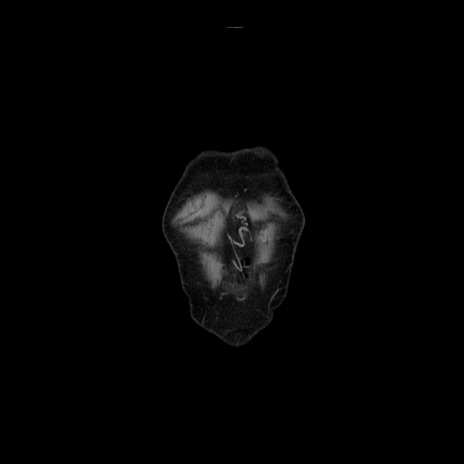

症例21(冠状断像)

【症例】70歳代男性

【現病歴】肝硬変・肝細胞癌にてかかりつけの方。約9時間前に食後より腹痛出現。症状が徐々に増悪し、嘔吐出現したため来院。

【既往歴】肝硬変、肝細胞癌(RFA、TACE後)